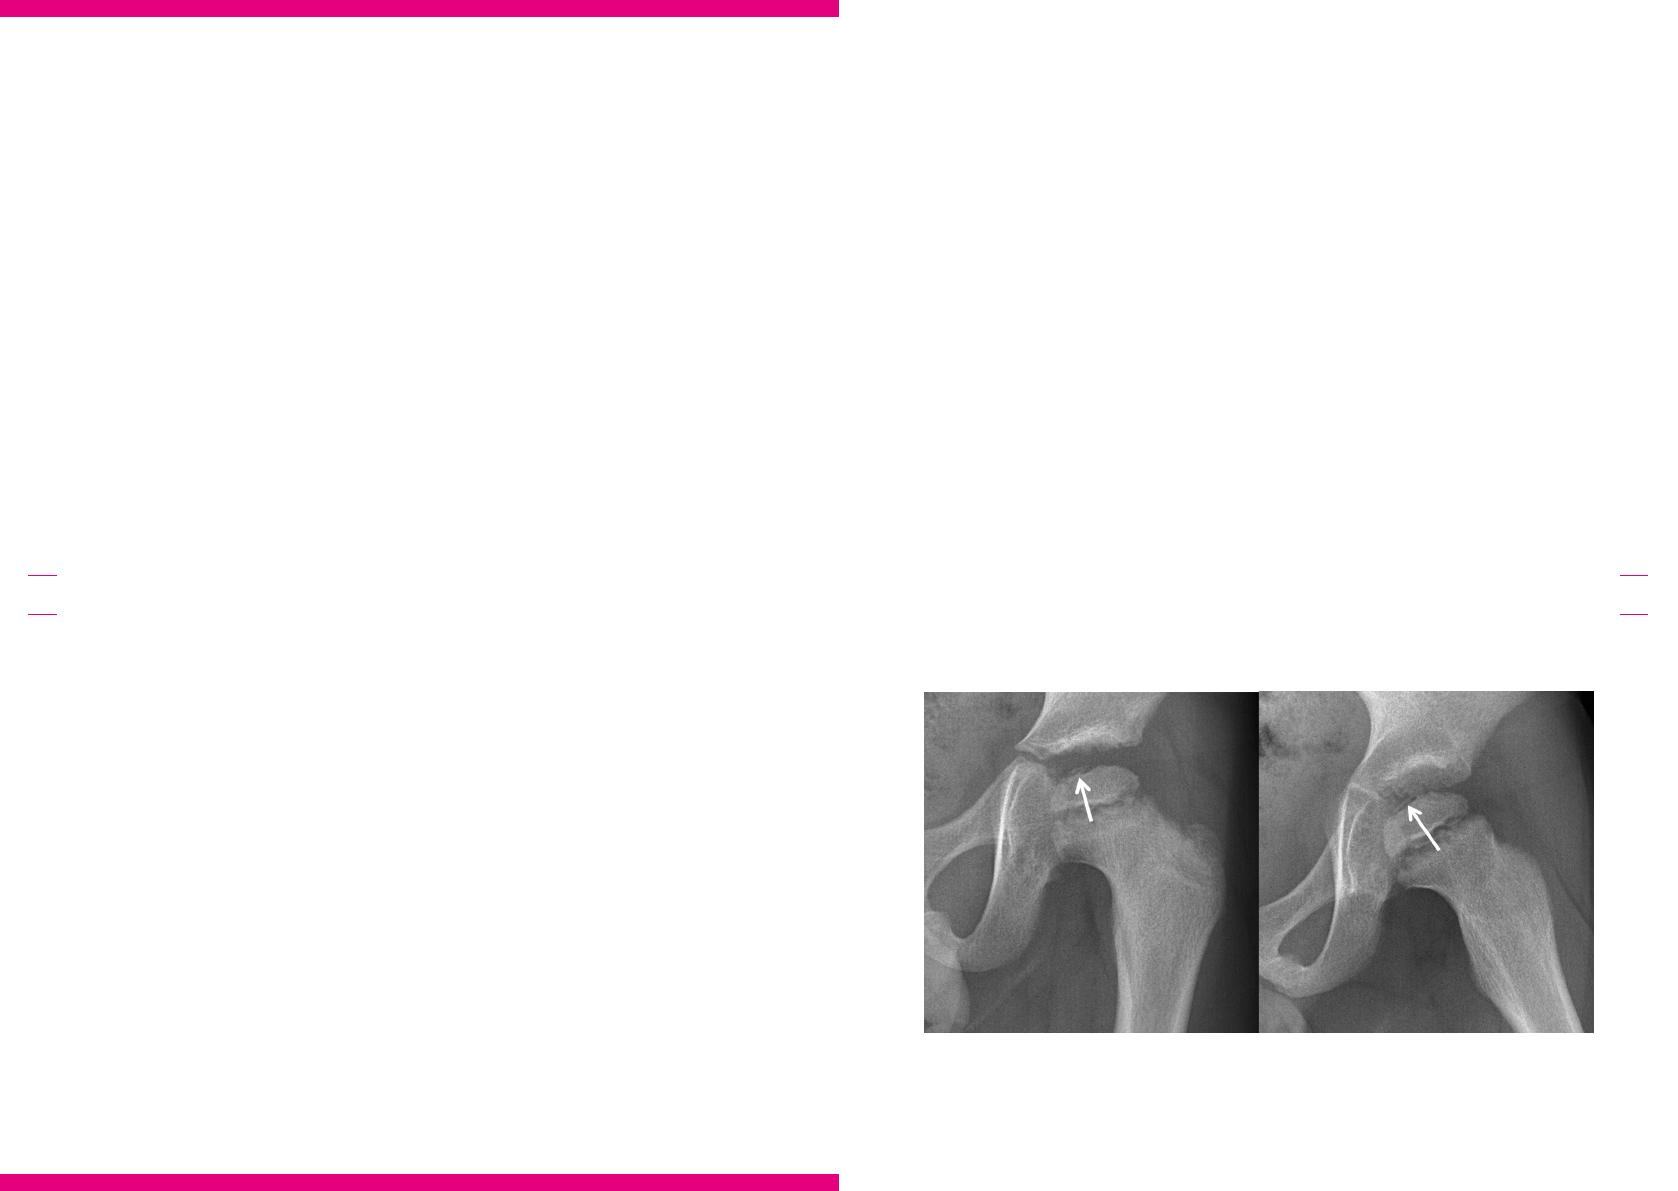

Face à un enfant âgé de 0 à 5ans, présentant une

boiterie sans signes cliniques d’infection, chez

qui les plaintes ne peuvent être localisées avec

exactitude, l’ACR estime qu’une radiographie de

la hanche (dose ecace <0,03 mSv) constitue

l’examen le plus pertinent (score de pertinence:

8), suivi d’une échographie de la hanche (score

de pertinence: 6). Si la radio de la jambe s’avère

négative, une radiographie en vue AP du pelvis,

du fémur et du pied (dose ecace: 0,03-0,3

mSv), une radiographie en vue AP et latérale

de la colonne vertébrale (0,03-0,3mSv), une

scintigraphie du squelette (0,3-3 mSv) et une

IRM de la colonne vertébrale thoraco-lombai-

re avec et/ou sans contraste se voient toutes

attribuer un score de pertinence de 5. Dans le

contexte belge, la première étape consistera à

combiner une radiographie avec une échographie

de la hanche, du genou et de la cheville afin de

vérifier la présence de liquide synovial. En cas

/

de plaintes localisées au niveau de la hanche ou

du genou, une radiographie et une échographie

de la hanche sont réalisées; une échographie de

la hanche négative sera suivie d’une évaluation

échographique de la cavité synoviale du genou

(Fig. 3).